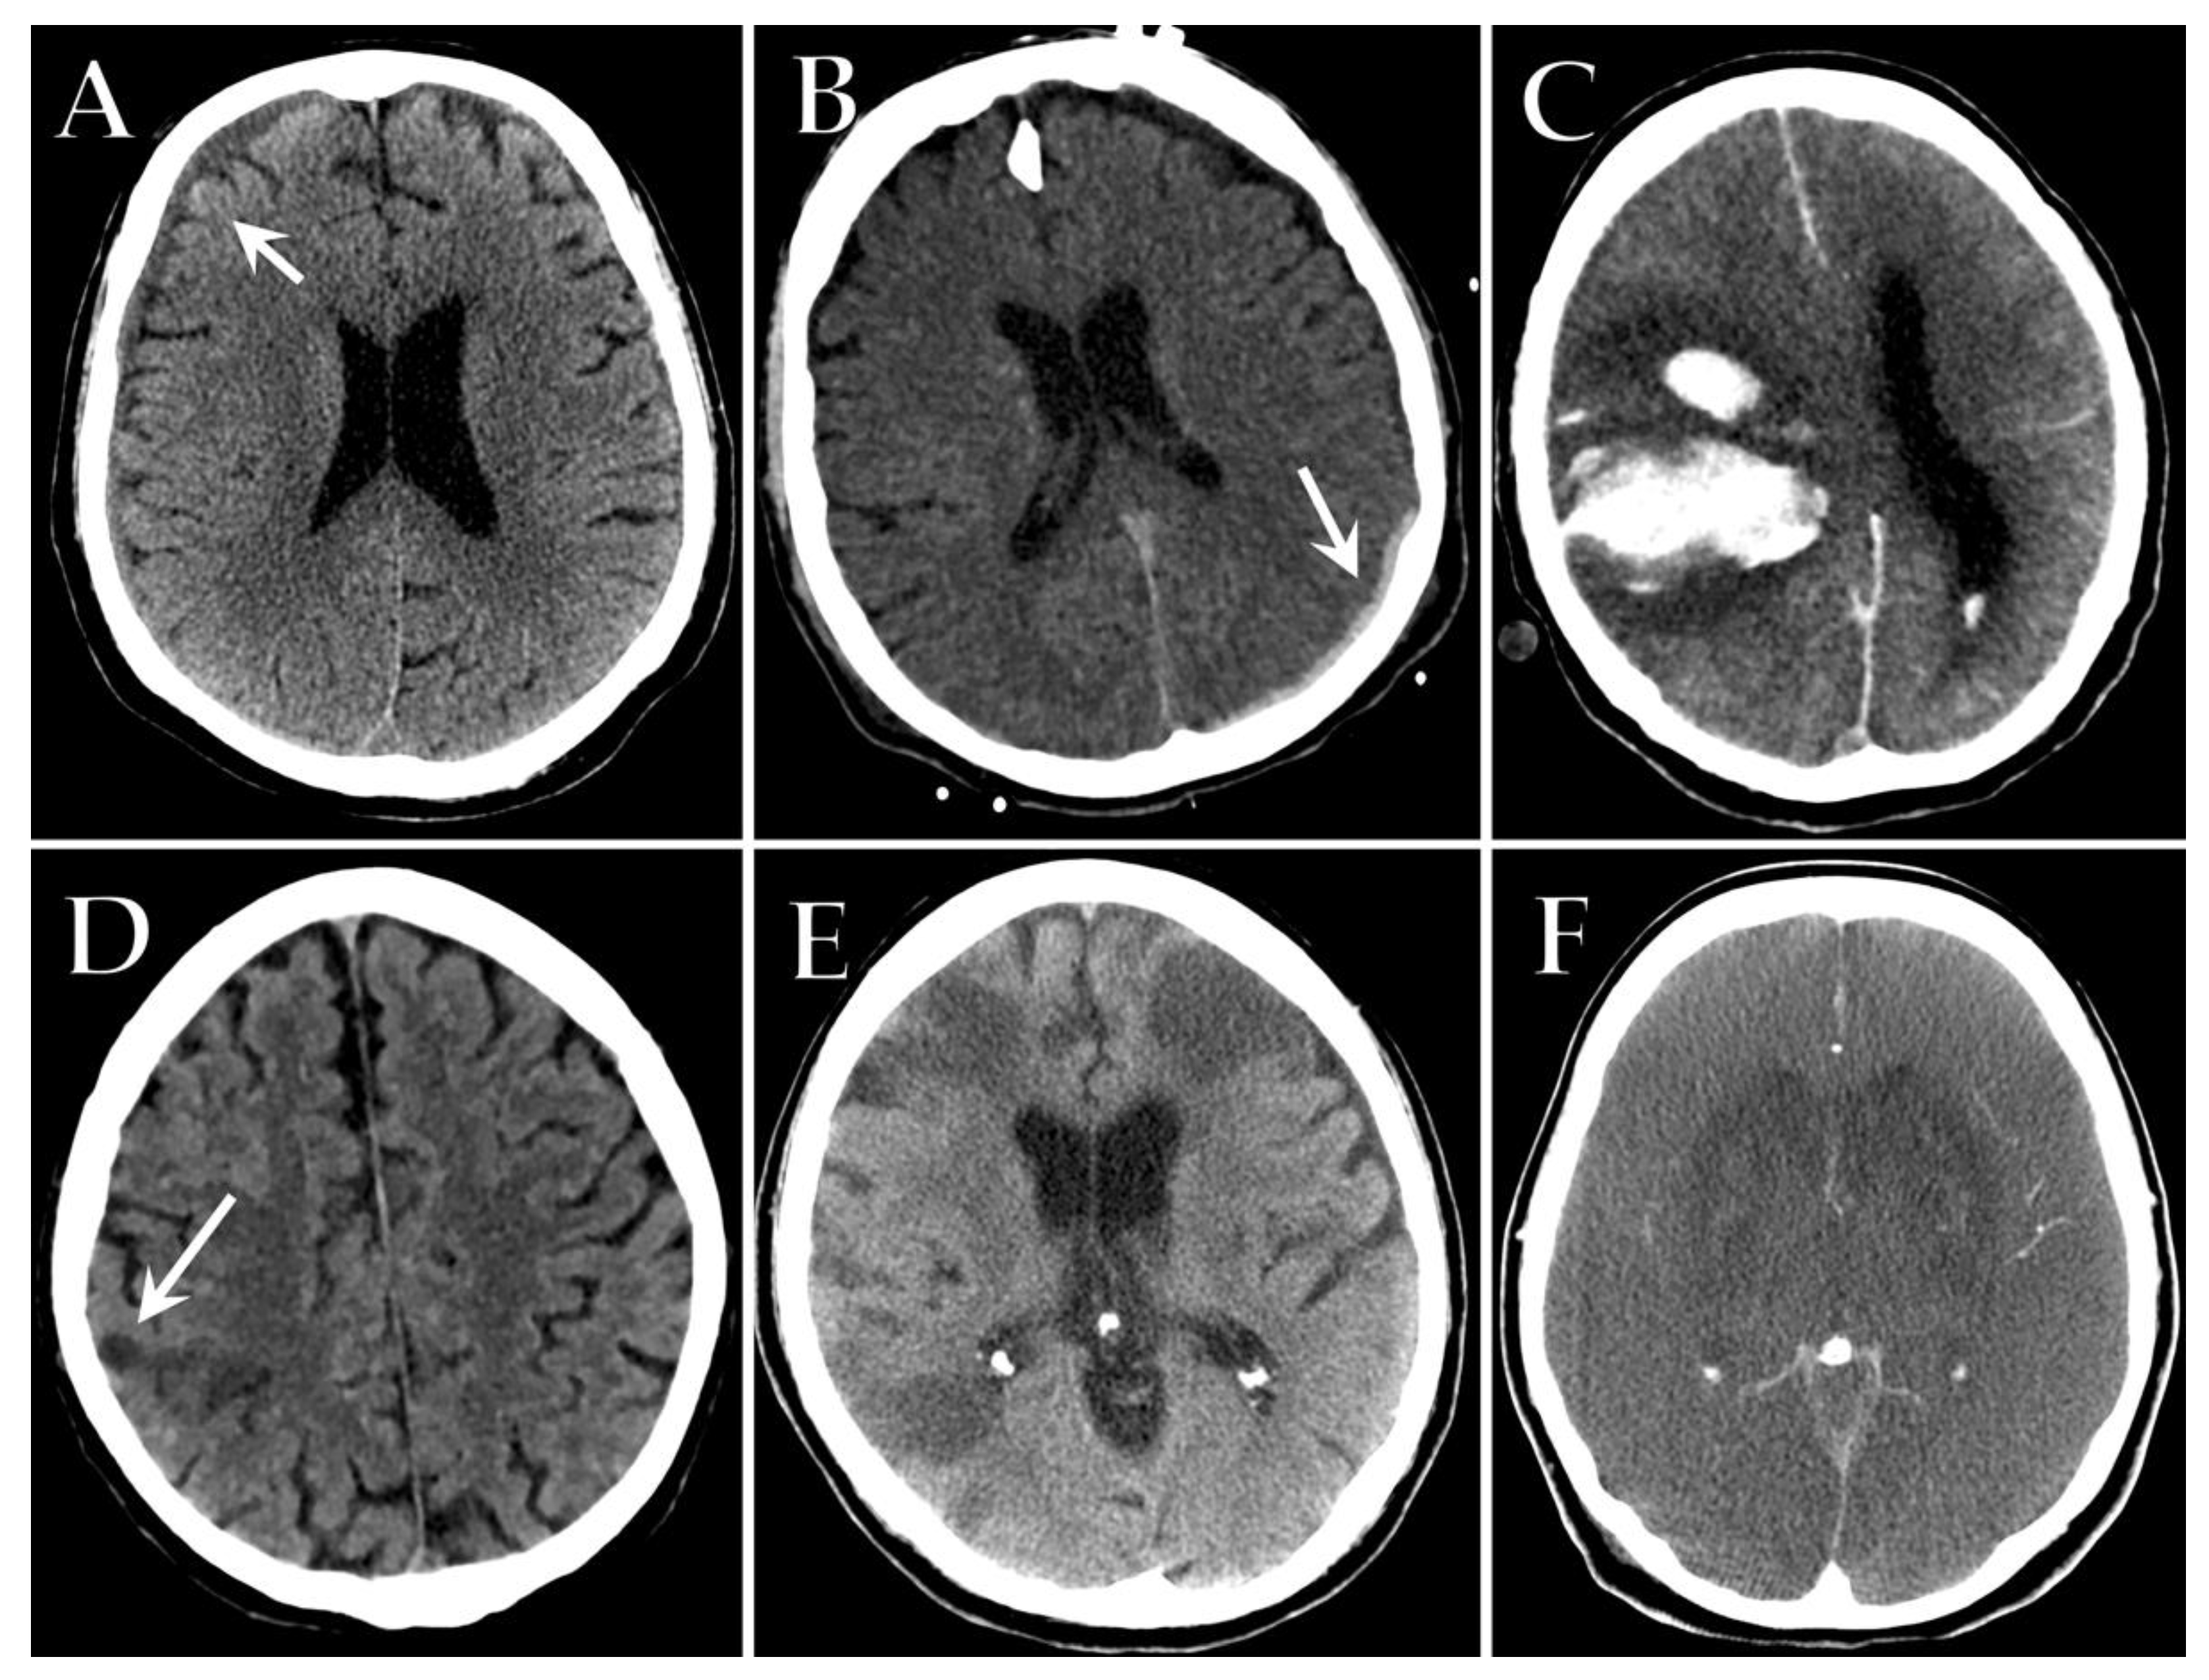

9. Neurological Complications

- Alves, V.D.P.V.; Altoé, A.; Veloso, V.; Ferreira, C.L.S.; Ventura, N.; Corrêa, D.G. Computed tomography features of cerebrovascular complications in intensive care unit patients with severe COVID-19. Radiol. Bras. 2021, 54, 283–288. [Google Scholar] [CrossRef]

- Sklinda, K.; Dorobek, M.; Wasilewski, P.G.; Dreżewski, K.; Dȩbicka, M.; Walecki, J.; Mruk, B. Radiological Manifestation of Neurological Complications in the Course of SARS-CoV-2 Infection. Front. Neurol. 2021, 12, 711026. [Google Scholar] [CrossRef]

- Vogrig, A.; Gigli, G.L.; Bnà, C.; Morassi, M. Stroke in patients with COVID-19: Clinical and neuroimaging characteristics. Neurosci. Lett. 2020, 743, 135564. [Google Scholar] [CrossRef] [PubMed]

- Heman-Ackah, S.M.; Su, Y.S.; Spadola, M.; Petrov, D.; Chen, H.I.; Schuster, J.; Lucas, T. Neurologically Devastating Intraparenchymal Hemorrhage in COVID-19 Patients on Extracorporeal Membrane Oxygenation: A Case Series. Neurosurgery 2020, 87, E147–E151. [Google Scholar] [CrossRef]

- Masur, J.; Freeman, C.; Mohan, S. A Double-Edged Sword: Neurologic Complications and Mortality in Extracorporeal Membrane Oxygenation Therapy for COVID-19–Related Severe Acute Respiratory Distress Syndrome at a Tertiary Care Center. Am. J. Neuroradiol. 2020, 41, 2009–2011. [Google Scholar] [CrossRef] [PubMed]

- Garg, R.K.; Paliwal, V.K.; Malhotra, H.S.; Sharma, P.K. Neuroimaging Patterns in Patients with COVID-19-Associated Neurological Complications: A Review. Neurol. India 2021, 69, 260–271. [Google Scholar] [CrossRef]

- Rapalino, O.; Pourvaziri, A.; Maher, M.; Jaramillo-Cardoso, A.; Edlow, B.; Conklin, J.; Huang, S.; Westover, B.; Romero, J.; Halpern, E.; et al. Clinical, Imaging, and Lab Correlates of Severe COVID-19 Leukoencephalopathy. Am. J. Neuroradiol. 2021, 42, 632–638. [Google Scholar] [CrossRef]

- Radmanesh, A.; Derman, A.; Lui, Y.W.; Raz, E.; Loh, J.P.; Hagiwara, M.; Borja, M.J.; Zan, E.; Fatterpekar, G.M. COVID-19—Associated Diffuse Leukoencephalopathy and Microhemorrhages. Radiology 2020, 297, E223–E227. [Google Scholar] [CrossRef]